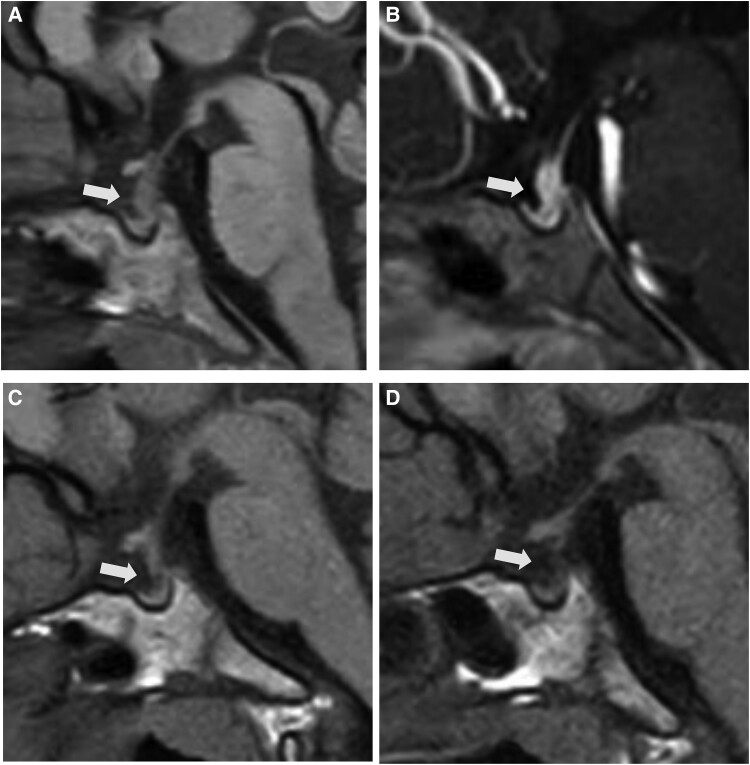

Lymphocytic infundibuloneurohypophysitis (LINH) is a disease with an etiology involving an autoimmune mechanism, characterized by lymphocytic inflammation of the posterior pituitary and infundibular stalk, resulting in arginine vasopressin deficiency. It is difficult to distinguish from pituitary neoplasm or infiltrative diseases, and biopsy is necessary for a definitive diagnosis, but this is highly invasive. In children, it is especially important to distinguish LINH from tumors such as germ cell tumors. Recently, the usefulness of anti-rabphilin-3A antibody as a serum marker for LINH has been reported. To date, only a limited number of pediatric cases have been reported. We present a 4-year-old boy with arginine vasopressin deficiency. Magnetic resonance imaging of the head showed thickening of the pituitary stalk without a posterior pituitary bright spot, and anti-rabphilin-3A antibody was positive. Consequently, pituitary biopsy was not performed because of the strong suspicion of LINH. Five months after symptom onset, the pituitary stalk thickening had resolved. This case represents the first report of probable or definitive LINH with anti-rabphilin-3A antibody positivity in a 4-year-old child, making it the youngest positive case reported to date. Our case highlights the importance of noninvasive approaches and careful follow-up to avoid invasive interventions for children with LINH.